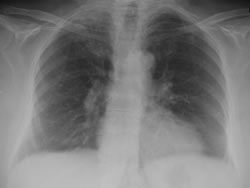

Imagen malapraxis-pulmonia

Los camaristas consideraron probada la “conducta omisiva” que cuando atendió a la joven, la profesional al limitarse a interrogarla, y “palpar la zona del pecho, sin auscultarla, y interpretar ligeramente el análisis de laboratorio, omitiendo la realización de placas radiográficas y nuevos estudios que permitieran determinar adecuada y temporariamente el cuadro que presentaba la joven y prescripción de un equivocado tratamiento, (medicación incorrecta, tratamiento ambulatorio, etc.) que tuvo como consecuencia el desenlace fatal constituye la mala praxis”.

Cabe recordar que la víctima concurrido en tres ocasiones a la clínica. La primera el 24 de diciembre y luego 4 días después, cuando fue atendida en el mismo día en dos ocasiones. La segunda, de las tres veces en que fue atendida, la médica imputada al atenderla “miró el análisis y dijo que se trataba de una falsa alarma” recetándole vitaminas y un tranquilizante, cuando en realidad la joven estaba padeciendo una severa infección respiratoria y sólo le funcionaba la cuarta parte de un solo pulmón.